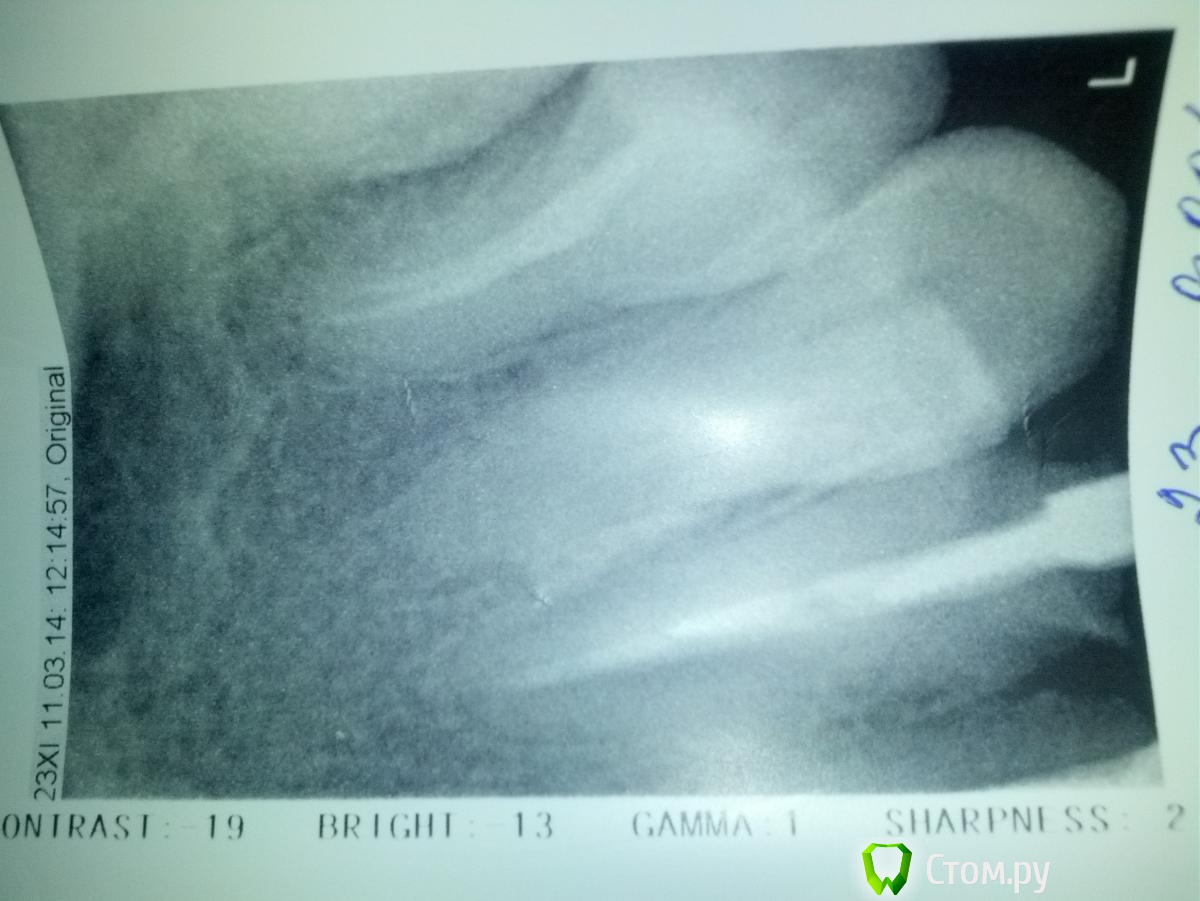

Занялась передними зубами, одного центрального резца нет, собираюсь поставить цирконий на 4 резца и клык. Сейчас возник вопрос, как лучше подготовить зубы под цирконивые коронки, если от зубов по сути остались только корни: 20 лет назад ставила пластик-сточили очень сильно (причем депульпировала здоровые зубы для эстетики :() , 11 лет назад поменяла на металокерамику, пришлось наращивать, сейчас меняю из-за синеватой полоски на уровне десны(показался метал) ...Сейчас врач просит нарастить еще для циркония, и поменять пломбы (судя по реакции терапевта-там одни пломбы и остались, коронковой части как таковой нет..врач-ортопед за стекловолоконные штифты (амортизируют лучше-говорит), терапевт, говорит, что лучше вкладок ничего не может быть, при таких разрушениях и что стекловолокно потом не достать..Хочу сделать отдельные коронки (ну кроме моста с отсутствующим резцом)..посоветуйте, пжл.что сделать:вкладки или стекловолокно... Сейчас в зубах стоят металлич.штифты (кроме одного, который сегодня вытащили и пока ничего не поставили)..К консенсусу ортопед и терапевт придти не могут, решение оставили за мной.